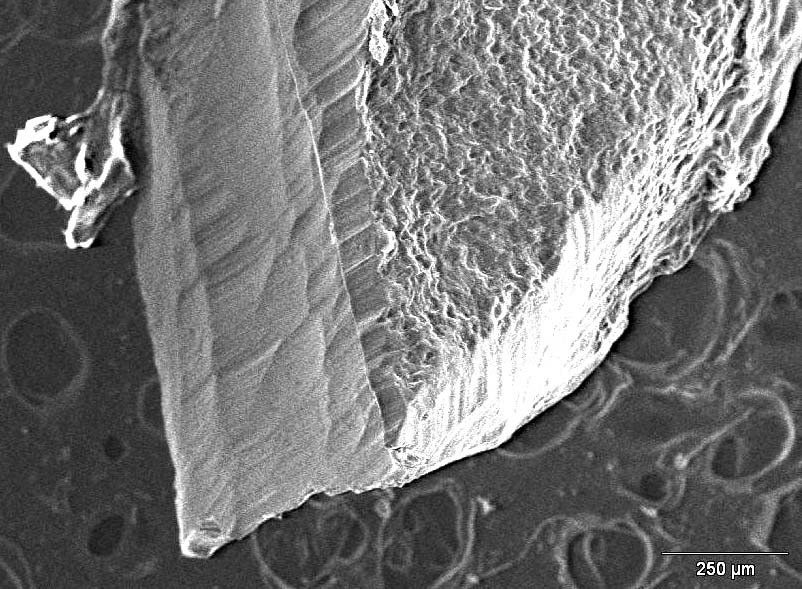

The areas of resorption of tooth #11, that presented with the fracture of the third apical portion of the root, are more limited and shallower than those observed on the root surface of tooth #21, which has been completely avulsed, where the resorption was more aggressive and the lesions appeared to be diffuse, destroying the root surface (Figure 7, Figure 8).

Figure 9 and Figure 10 show the surface of the 2 removed apical fragments of tooth #21 and #11, respectively. Interestingly, the surface of the fracture that is visible on the apical root fragment removed during the apicoectomy of #11 is characterised by the presence of regular steps, reflecting a repetitive pattern.

Micrographs are taken and energy dispersive spectroscopy (EDS) analysis is performed in the step regions in order to provide further information on fracture modality. Chemical analysis (microanalysis) with SEM can be performed by measuring the energy distribution and X-ray intensity generated by an electron beam on the sample using the EDS. This enables to identify and quantify the chemical elements in a given surface. The analysis indicates the percentage changes in the composition of phosphorus (P) and calcium (Ca) along the selected line, respectively, on the horizontal side (Figure 11) and on the vertical side (Figure 12) of one of the steps visible on the fracture surface. The point analysis, carried out at 7 measuring points selected along the tested lines, also confirms the stability of the P and Ca percentages. The analysis of microanalytical maps of the element distribution clearly emphasizes the heterogeneity in the transition areas between the horizontal and vertical parts.